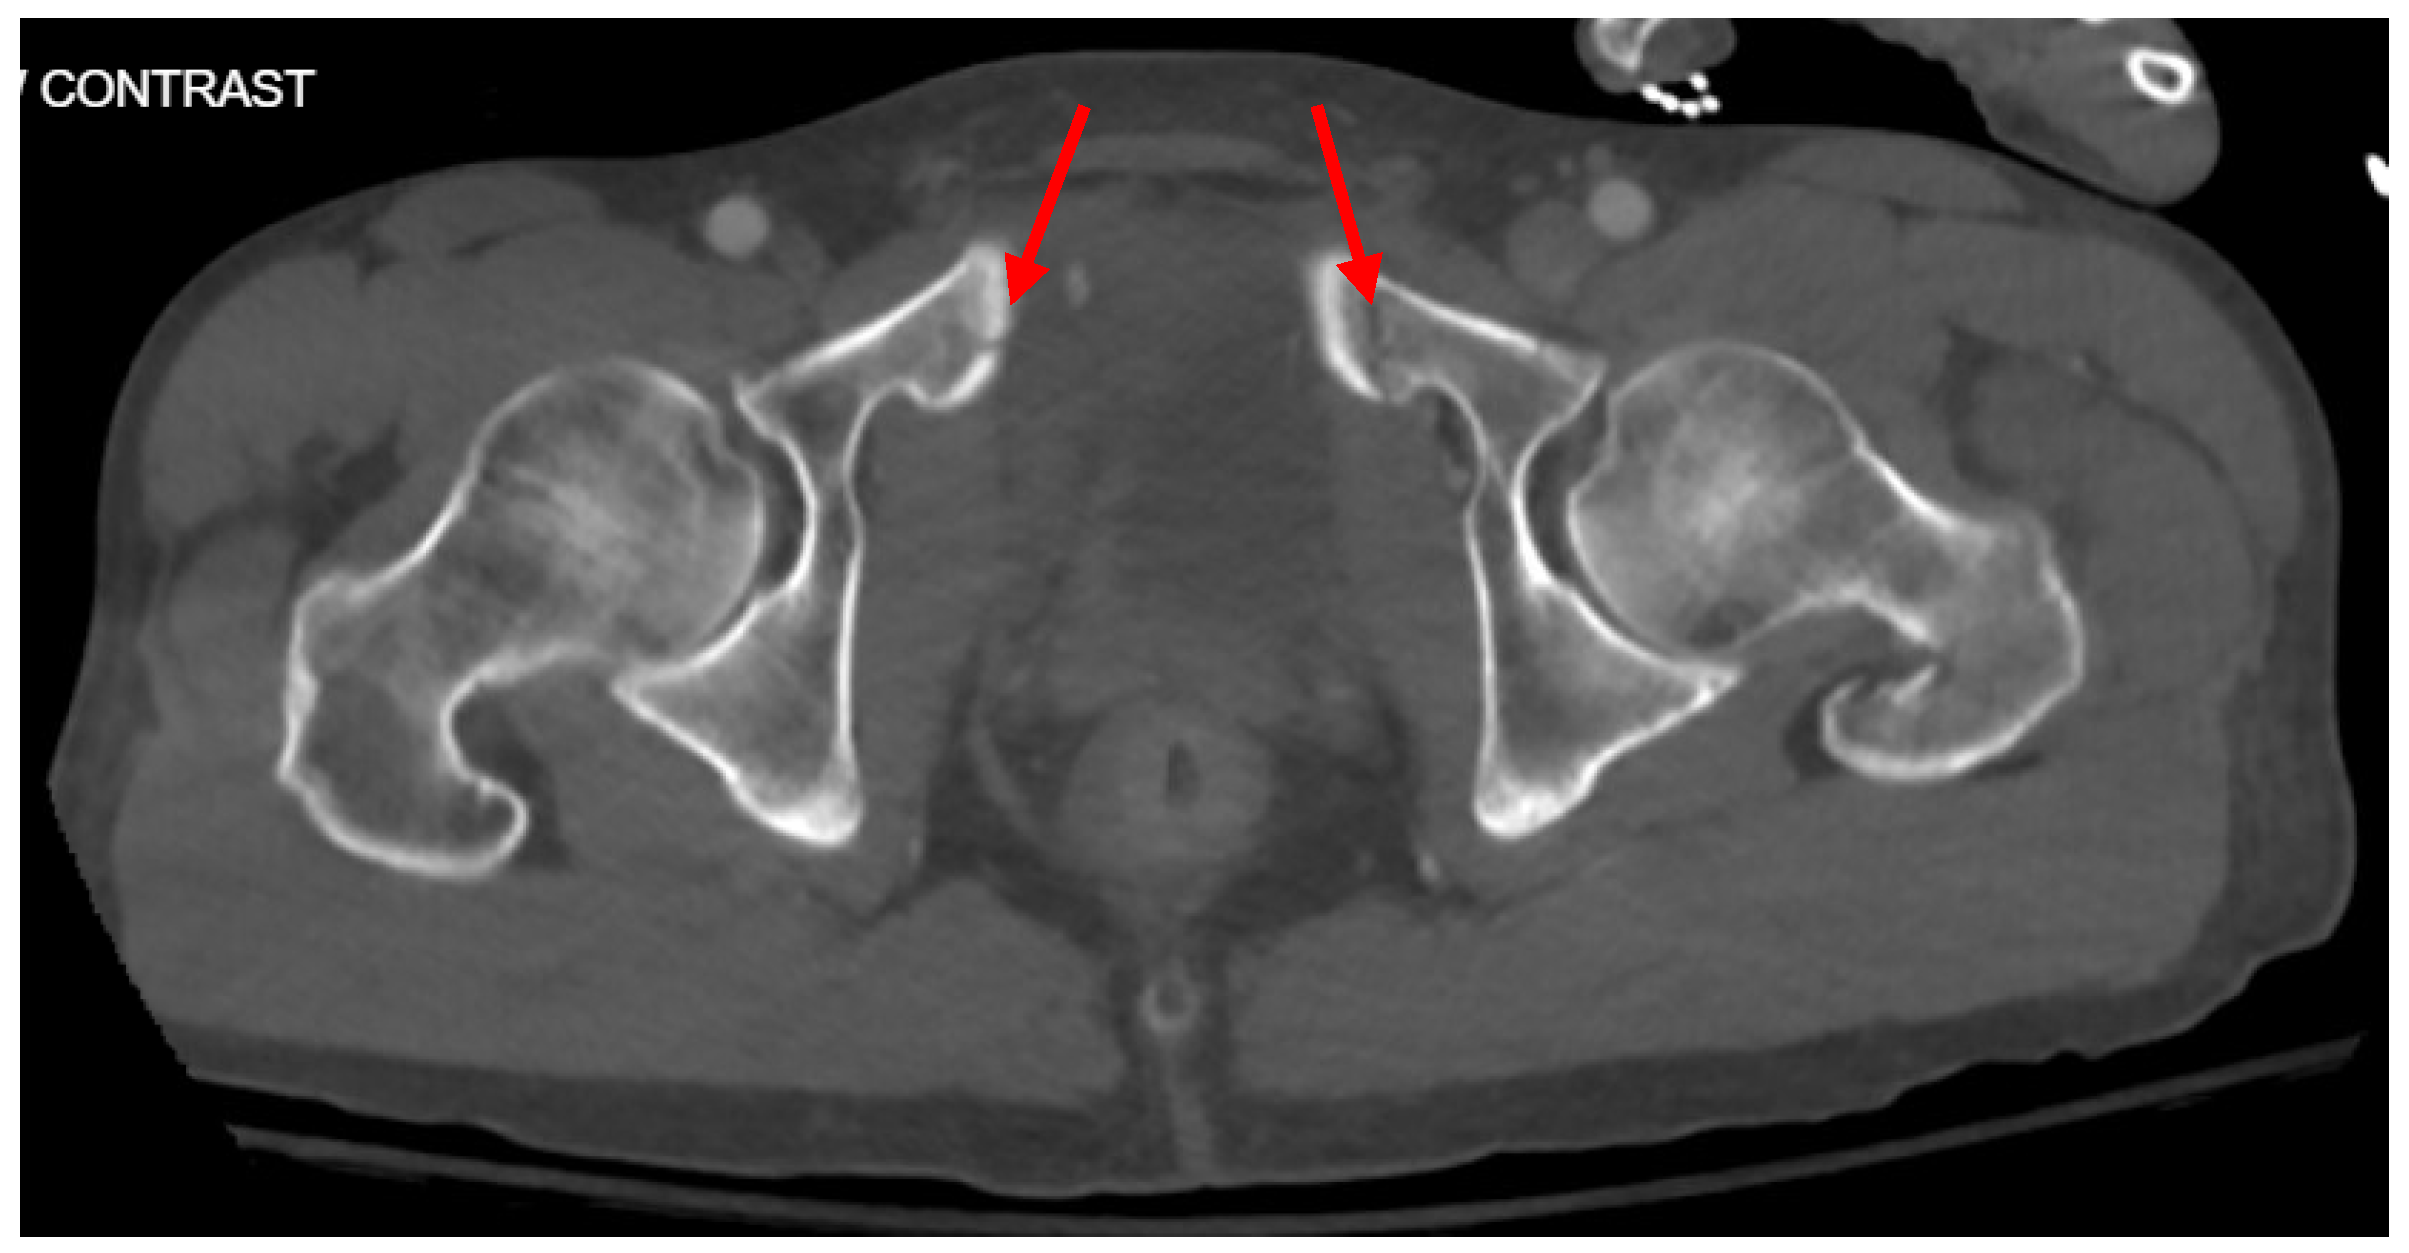

Pelvic imaging revealed acute fractures involving the right superior pubic ramus and left inferior pubic ramus, an acute comminuted avulsed fracture of the left sacral wing in the superior and midportion (Figure 1). Additional injuries included multiple facial fractures, left distal radius fracture, left femur fracture, and left tibial shaft fracture.

Figure 1. CT abdomen/pelvis images of the described fractures in case 1. Red arrows are used to indicate the location of pelvic fractures for easier identification.